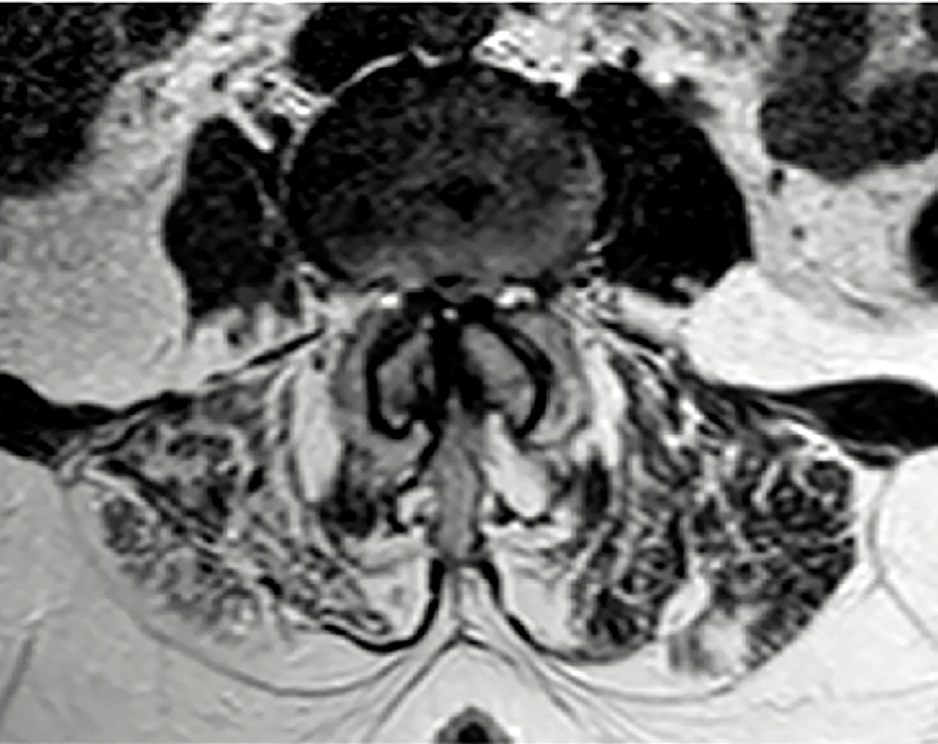

A su llegada se realiza una TC que muestra anterolistesis L3-L4 y L4-L5 y retrolistesis L5-S1, mientras que la RMN (Figs. 1 y 2) confirma una estenosis de canal severa en niveles L2-L3 y L3-L4, similar a estudios previos (Figs. 3 y 4)

Se sospecha síndrome de cola de caballo subagudo secundario a la estenosis crónica. Inicialmente, debido al alto riesgo quirúrgico, se opta por tratamiento conservador con analgesia, corticoterapia y vigilancia hospitalaria.

En este caso, la dificultad radica en el equilibrio entre el riesgo quirúrgico elevado, la clínica vesical establecida y la falta de traducción de la clínica en la imagen radiológica, destacando la importancia de la valoración clínica en estos pacientes.